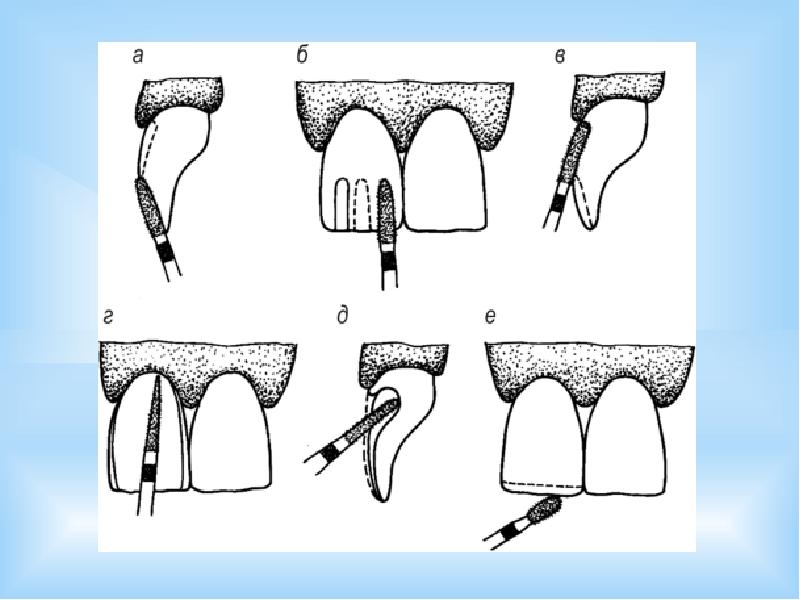

Культя зуба это

Культя зуба это 106 фото